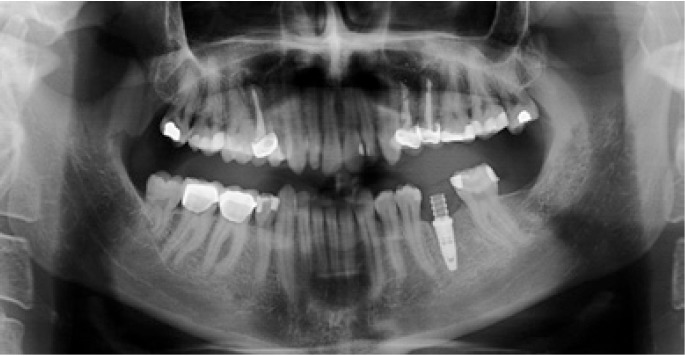

Figure 2.

Preoperative panoramic X-ray view.